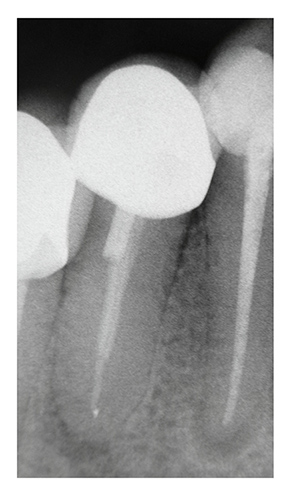

Zementierte, geschraubte Metallstifte, die maximal in das mittlere Kanaldrittel reichen, lassen sich in der Regel gut radiologisch beurteilen und bieten häufig günstige Voraussetzungen für eine kontrollierte Entfernung (Abb. 1).

Abb. 1: Zahn 45 mit relativ kurzem, geschraubtem Metallstift | Foto: Franziska Haupt